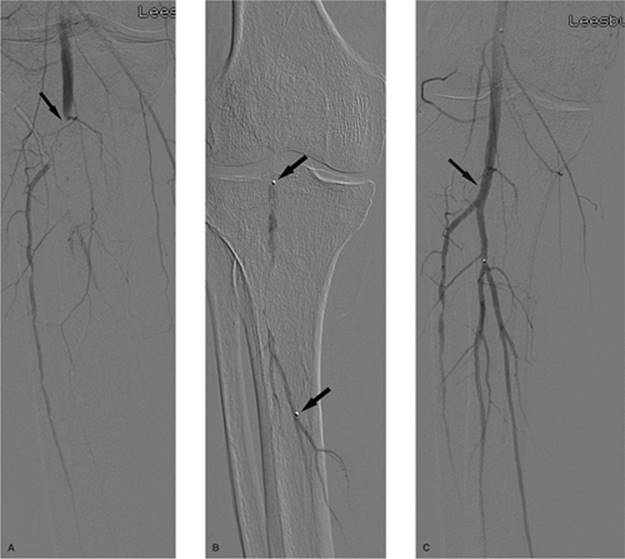

000640

Figure 35.26. Contrast injection of the right internal jugular vein shows complete occlusion at the level of the base of the neck (white arrow).

000643

Figure 35.27. Same patient as in Figure 35.26. Access has been obtained across the area of obstruction, and balloon angioplasty is being performed with a 14-mm balloon (black arrow).

000644

Figure 35.28. Postangioplasty contrast injection demonstrates improved flow in the superior vena cava (black arrow).

000269

Figure 35.29. Successful placement of a tunneled dialysis catheter (black arrow) in a previously occluded right internal jugular vein. This is the same patient as in Figures 35.26–35.28.

000647

Figure 35.30. Contrast injection of the left internal jugular vein shows complete occlusion of the innominate vein (black arrow).

000651

Figure 35.31. Successful revascularization of the previously occluded innominate vein with placement of a tunneled dialysis catheter by this left internal jugular venous approach.